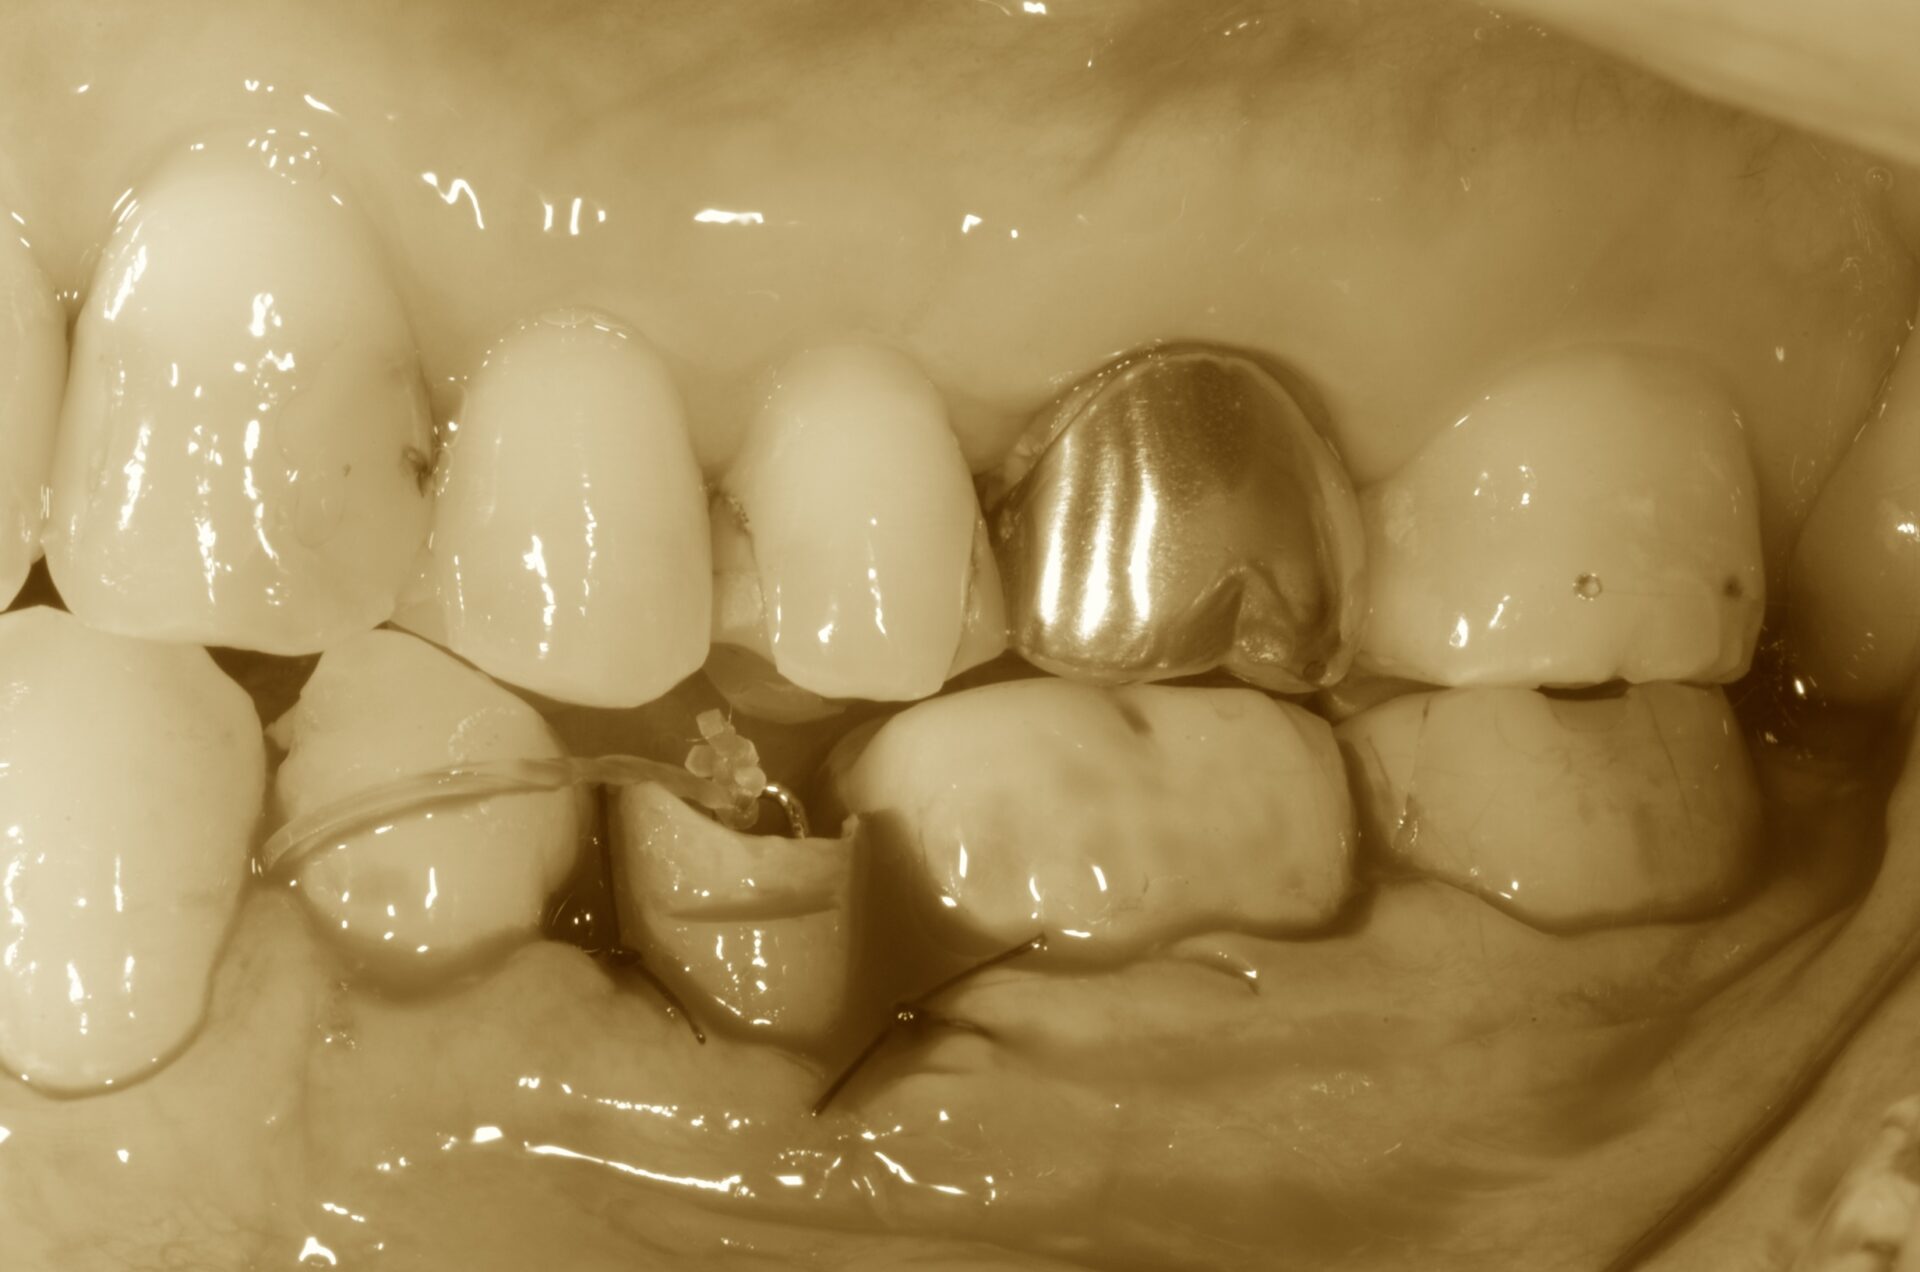

牽引開始

牽引レントゲン